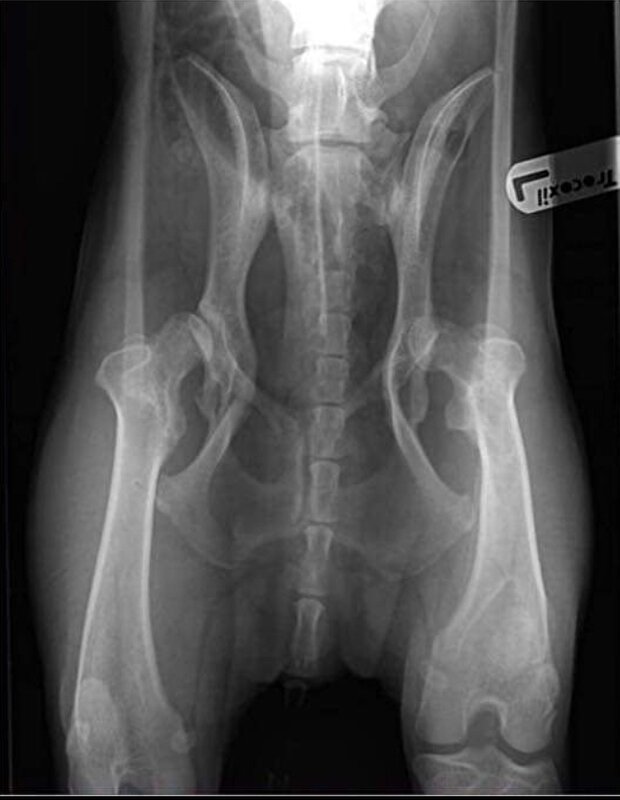

Het betreft een grote DH reu, maar ook echt groot, nu al.

Afbeelding

och arme wat doen ze dat beestje aan zeg

edit ik zou dat beestje dus laten gaan, dit is toch niet dierwaardig zoveel sleutelen.

Oké dan … even nieuwe heupkommen.